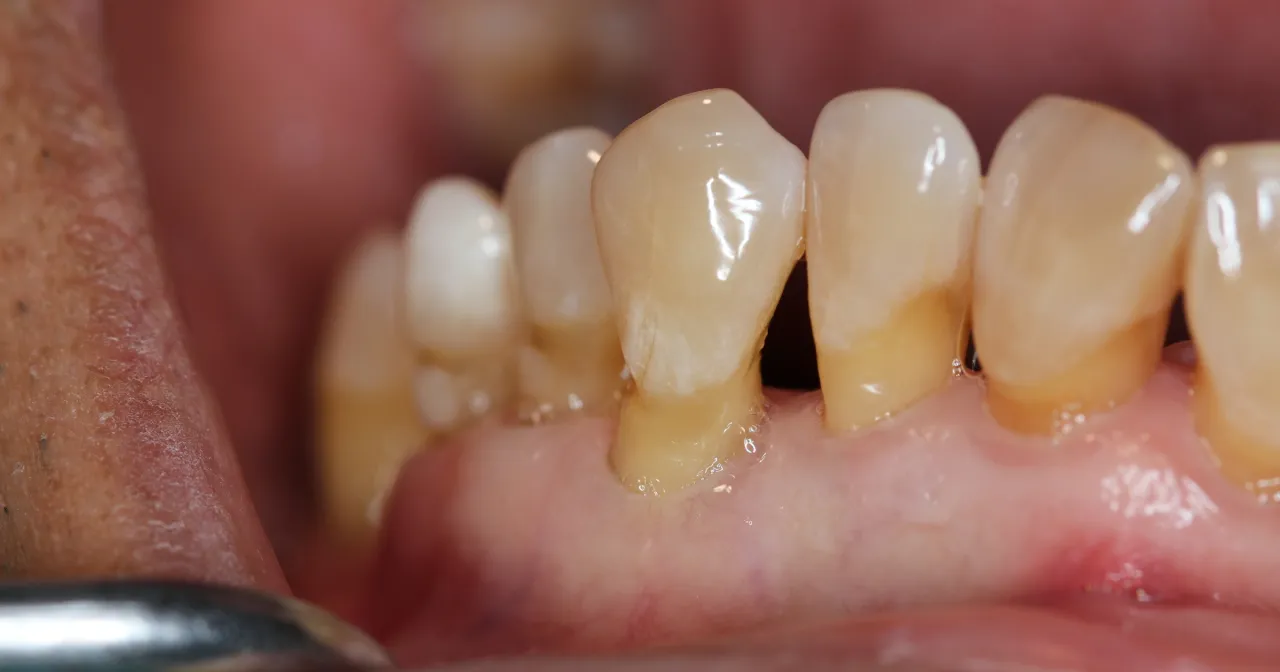

Recesja dziąseł to proces, w którym tkanka dziąsłowa stopniowo odsuwa się od korony zęba, odsłaniając jego szyjkę, a w bardziej zaawansowanych przypadkach również korzeń. Wizualne "wydłużenie zębów" jest często pierwszym i najbardziej charakterystycznym symptomem, który zauważają moi pacjenci. To sygnał, którego absolutnie nie należy lekceważyć, ponieważ odsłonięte części zęba są znacznie bardziej podatne na próchnicę, ścieranie i nadwrażliwość, a także mogą świadczyć o poważniejszych problemach z przyzębiem.

- Zmiana koloru przy linii dziąseł: Odsłonięta zębina ma naturalnie ciemniejszy, często bardziej żółty kolor niż białe szkliwo korony zęba. Ta różnica w odcieniu staje się widoczna, gdy dziąsło się cofa.

- Ubytki klinowe: To charakterystyczne wgłębienia lub nacięcia, które pojawiają się tuż przy szyjkach zębów, w miejscu, gdzie dziąsło styka się z zębem. Często są one wynikiem zbyt agresywnego szczotkowania zębów, co jest również jedną z przyczyn recesji.

Recesja dziąseł to proces dynamiczny, który może postępować w różnym tempie. Zaczyna się często od dyskretnych objawów estetycznych, takich jak wizualne wydłużenie zębów, oraz od nadwrażliwości na bodźce. W miarę postępu choroby, odsłonięcie korzeni staje się coraz większe, a ryzyko próchnicy korzenia i ubytków klinowych wzrasta. W najbardziej zaawansowanym stadium, gdy dochodzi do znacznego zaniku kości i aparatu utrzymującego ząb, może pojawić się nawet ruchomość zębów. Wczesne wykrycie i interwencja są kluczowe dla zatrzymania progresji i skuteczności leczenia.